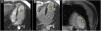

Varón de 57 años con antecedente de infarto de miocardio anterior. En una tomografía axial computarizada (TAC) cardíaca realizada 3 años más tarde, se objetiva una imagen hipodensa en el ápex del ventrículo izquierdo. Ante la sospecha de trombo, se completa el estudio mediante resonancia magnética cardíaca (RMC) con gadolinio, ecocardiografía transtorácica (ETT) 2D con ecopotenciador y ETT tridimensional. A través de la imagen multimodalidad se comprueba la ausencia de trombo.

Cardiac computed tomography showed a hypodense area in the apex of the left ventricle in a 57-year-old man with a history of anterior myocardial infarction three years earlier. To confirm or rule out a suspected thrombus, he underwent gadolinium-enhanced cardiac magnetic resonance imaging, contrast-enhanced two-dimensional transthoracic echocardiography, and three-dimensional transthoracic echocardiography. Multimodality imaging ruled out the presence of a thrombus.